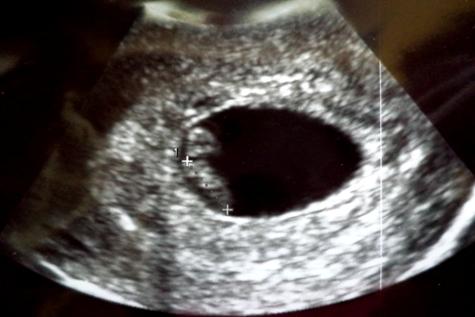

@lolo8280: Nagyon szép kis formás. Nem látszik még, hogy kettő baba lenne

Köszönjük a fotót ![]()